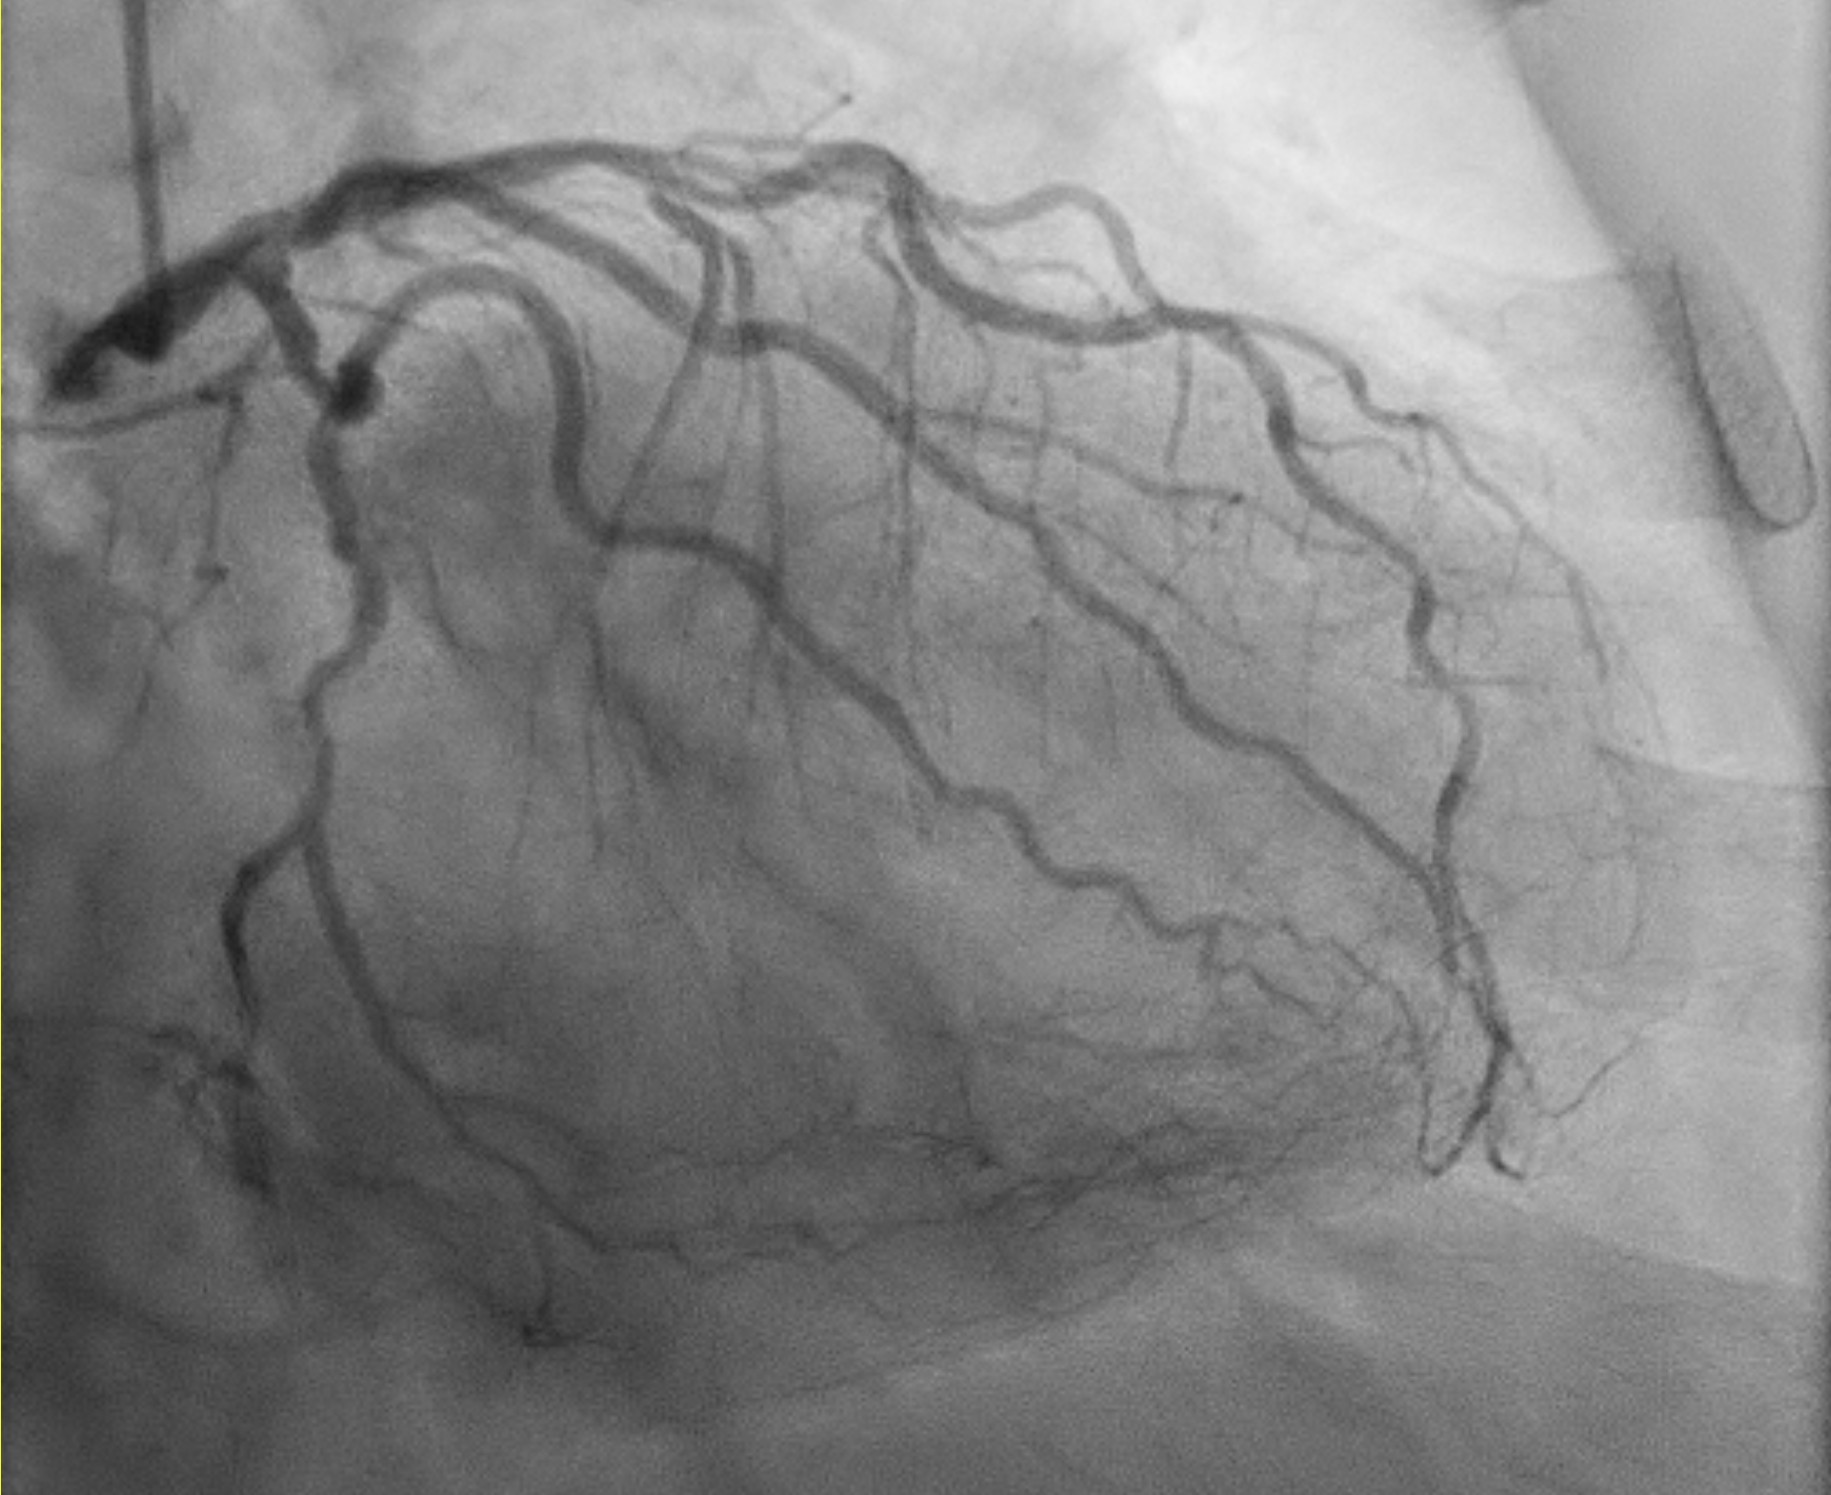

TRA diagnostic angiogram (pictures 1-3) showed mild distal LMS. Mild proximal-mid LAD stent <20% ISR and distal LAD 50% stenosis. Distal circumflex 50% stenosis. Proximal RCA 90% stenosis, distal 70% (segment 3) and then followed by total occlusion. Distal RCA received collaterals from LCA. Results discussed with patient who agreed for elective angioplasty to RCA.